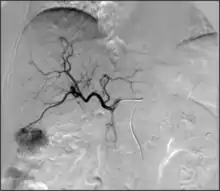

- Angiography: Imaging the blood vessels to look for abnormalities with the use of various contrast media, including iodinated contrast, gadolinium based agents, and CO2 gas.[3]